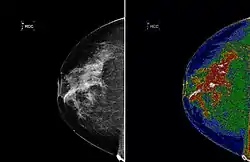

A region of interest (often abbreviated ROI) is a sample within a data set identified for a particular purpose.[1] The concept of a ROI is commonly used in many application areas. For example, in medical imaging, the boundaries of a tumor may be defined on an image or in a volume, for the purpose of measuring its size. The endocardial border may be defined on an image, perhaps during different phases of the cardiac cycle, for example, end-systole and end-diastole, for the purpose of assessing cardiac function. In geographical information systems (GIS), a ROI can be taken literally as a polygonal selection from a 2D map. In computer vision and optical character recognition, the ROI defines the borders of an object under consideration. In many applications, symbolic (textual) labels are added to a ROI, to describe its content in a compact manner. Within a ROI may lie individual points of interest (POIs).

A ROI is a form of Annotation, often associated with categorical or quantitative information (e.g., measurements like volume or mean intensity), expressed as text or in a structured form.